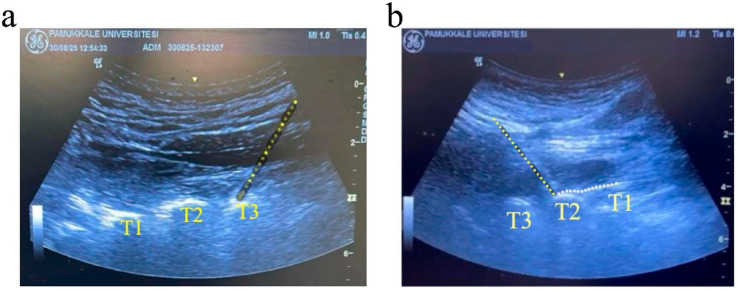

Background/Objectives: High thoracic erector spinae plane block (ESPB) is a novel technique for managing chronic radicular and sympathetically mediated pain. Although physiological changes, such as increased skin temperature, perfusion index (PI), and optic nerve sheath diameter (ONSD), are known to reflect ESPB-induced sympatholysis, their predictive value for analgesic success remains unclear. In this context, the objective of this study is to investigate whether these objective indicators of sympathetic blockade are associated with the clinical success of high thoracic ESPB. Methods: The sample of this prospective, observational study consisted of 35 adult patients with chronic radicular pain undergoing a high thoracic ESPB procedure. Pre- and post-procedure assessments included bilateral skin temperature, PI, ONSD measurements, and administration of a visual analog scale (VAS). Patients with a greater than 50% decrease in VAS score were deemed responders to the procedure. Results: Of the 35 patients, 29 (82.9%) were responders. The patients' post-procedure ipsilateral skin temperature (p < 0.001), PI (p = 0.002), and ONSD (p < 0.001) values were significantly higher than their pre-procedure values. However, none of these parameters differed significantly between responders and non-responders (p > 0.05). There was also no significant correlation between VAS score and changes in PI, ONSD, or skin temperature (p > 0.05). Conclusions: In conclusion, although high thoracic ESPB resulted in measurable physiological changes suggestive of sympathetic blockade, these changes did not predict clinical analgesic success.